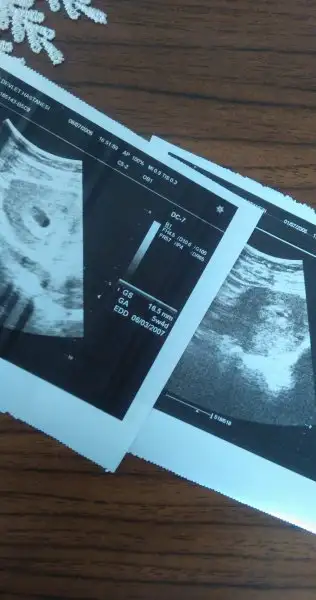

5+ 3 te benim sadece kese görünmüştü bebeği görememiştik.ben açıkcası o ölçümleri hiç dikkate almıyorum.çok fazla kafana takma derim.slm kızlar moralim çok bozuk bugün hastaneye gittim normalda 6. haftamda olmam gerekiyodu gecen hafta carşamba günü gittigimde 5+3 günlüktü neyse bugün ultrasona girdim bana demesin mi 5+4 günlük ama gecen hata aynıydı hiç büyümemişmi kese hem bebek de ozaman pazartesi günü gözükürdü demiştiniz dedim. yok ben kese demişimdir falan dedi çok moralim bozuldu 3 hafta sonra gel dedi. neyse ben eve gelince gecenki ultrason kagıdıyla bugünkünü karşılaştırdım bir hafta önceki kese küçüçük bişeymiş ama bugünkü baya büyük sanki içinde bebekde var gibi bilmiyorum gercekten çok kafam karıştı hani gec döllenme olayı falan desem öyle olmadıgına eminim

Geçen haftakinde kese kaç mm görünüyor? Bu hafta 16,5 mm olmuş galibabuda ultrason fotosu alttaki bir hafta önceki üstteki bugünkü

Geçen haftakinde kese kaç mm görünüyor? Bu hafta 16,5 mm olmuş galiba

alet veya ölçüm farkıdır bence.içini ferah tut.canım aslında bende kafama takmıyordum ama bir hafta hiç büyümemiş acaba gelişimi mi durdu diyorum of kafamda deli sorular